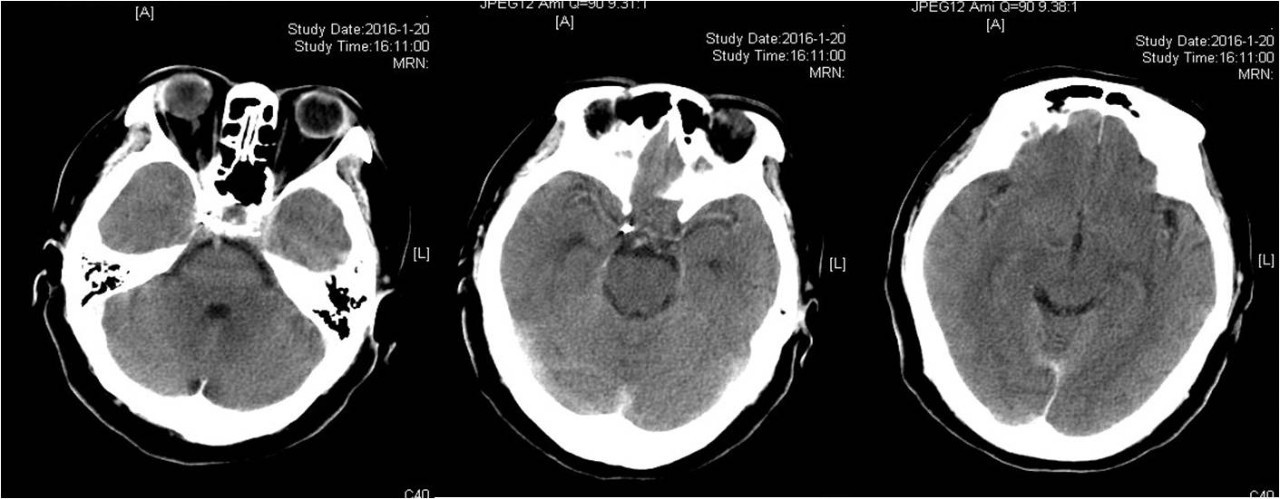

病例2:后交通动脉动脉瘤(Pcom-An)

》女性,59岁,因一过性意识不清伴头痛20天入院,头痛为全头炸裂样疼痛,于当地医院检查后诊断为“蛛网膜下腔出血”保守治疗20天,现仍有头痛,为求进一步诊治入院。既往有高血压病病史40年,血压控制不详。

》入院时查体:项强3横指。

术前、术后DSA对比

》DSA检查发现右侧后交通动脉动脉瘤,全麻下行颅内动脉瘤栓塞术。

术后即刻复查头颅CT

》术后即可复查头颅CT未见蛛网膜下腔出血。